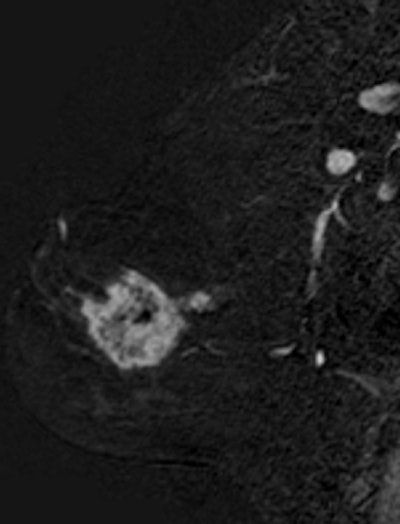

Breast cancer staging in a 42-year-old woman using sagittal 3D sequence with gadolinium chelates injection, subtraction. A bifocal lesion is seen on this view. The size of the largest lesion was 50 mm. Mammography and ultrasound only depicted a unique 40-mm lesion. Breast MRI can be a valuable imaging tool for staging lobular infiltrative carcinoma, as in this case. Image courtesy of Dr. Corinne Balleyguier.